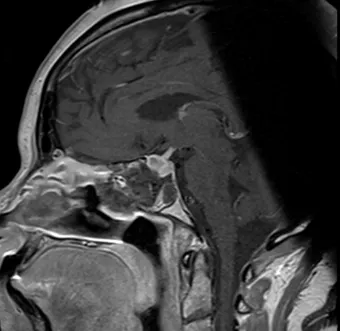

Pre- and Post-Op Pituitary Macroadenoma

Pre-Op Pituitary Tumor Image 2

Pre-Op Image of Pituitary Tumor